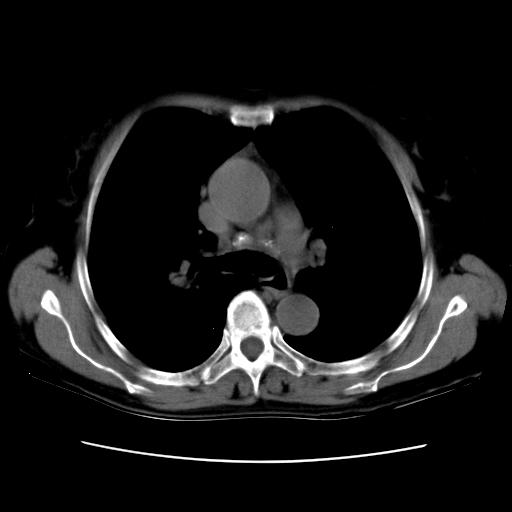

以下是引用卜一在2007-9-18 14:41:00的发言:[br]右肺肿块:毛刺+胸膜凹陷征+供血血管+浅分叶+强化。支持:周围性肺癌 !另:左侧甲状腺腺瘤!

以下是引用夏季在2007-9-18 11:00:00的发言:[br]1。右肺肿块,周围有短毛刺,肺门侧有血管与其相连,胸壁侧有胸膜凹陷征,考虑周围性肺癌 2。左侧甲状腺软组织肿块,内有高密度钙化灶,考虑左侧甲状腺腺瘤。